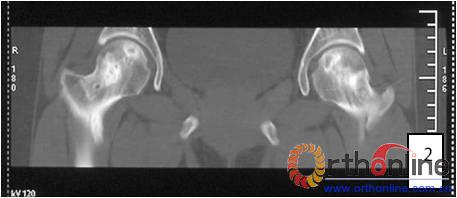

2.2 影像学结果 影像学结果与临床结果基本同步。临床结果优的36髋,34髋维持圆形且修复较完全(图1)。1例双髋Ⅲa激素性(SARS患者)ONFH,术后随访7年8月,X线片显示股骨头虽不圆,但临床HHS评分90分为优(图2)。功能为良的12髋,7髋股骨头不圆,但股骨头与髋臼匹配好,其余5髋股骨头维持圆形。临床评定为差的17髋,股骨头均有超过4mm塌陷,股骨头与髋臼匹配不好,股骨头内无折断,MRI未显示骨髓水肿,关节间隙呈不对称改变,CT扫描示软骨下骨折,MRI显示骨髓水肿。

图2 男,22岁,激素性骨坏死,(1)双侧股骨头骨髓水肿,ARCO分期Ⅲa期,C3型;(2)X线片示股骨头塌陷,术前关节功能差(Harris评分50分);(3)打压植骨术(未加BMP2)后7年,关节功能好(Harris评分90分),股骨头有轻度塌陷,但头臼匹配好;(4)蛙式位显示股骨头臼匹配好